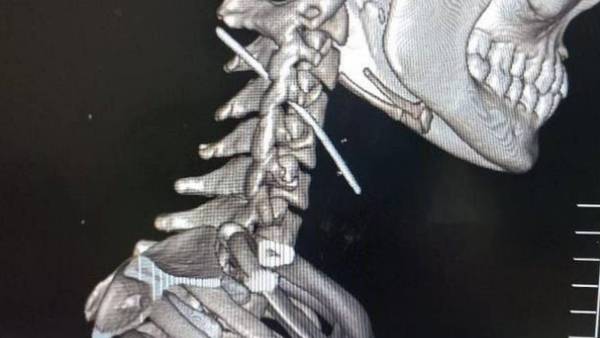

கோவை : தற்கொலைக்கு முயன்ற பெண் ஒருவர் கழுத்தில் 8 செமீ தையல் ஊசியை

குத்திக்கொண்டார். அவருக்கு கோவை மருத்துவர்கள் அபார அறுவை சிகிச்சை செய்து காப்பாற்றி உள்ளனர்.

நவம்பர் 2ம் தேதி கழுத்தில் படுகாயங்களுடன் பெண் ஒருவர் கோவை அரசு மருத்துவக் கல்லூரி மருத்துவமனையில் ஆபத்தான நிலையில் அனுமதிக்கப்பட்டார். தற்கொலைக்கு முயன்ற அந்த பெண் விஷம் குடிக்கவில்லை, தூக்கில் தொங்கவில்லை,

கழுத்தை அறுத்துக்கொள்ளவில்லை. அதற்குப் பதிலாக சுமார் 8 சென்ட்டி மீட்டர்

நீளம் உள்ள தையல் ஊசியை எடுத்து கழுத்தில் குத்திக்கொண்டுள்ளார்.

மருத்துவர்கள் பின்னர் சிடி ஸ்கேன் எடுத்துப் பார்த்தப் பின்னர் அதிர்ச்சி

அடைந்தனர். அந்த ஸ்கேன் ரிப்போர்ட் பெண்ணின் கழுத்துப் பகுதியில் சுமார் 8

சென்டி மீட்டர் நீளமுள்ள தையல் ஊசி இருப்பதைக் காட்டியது.

மூச்சுக் குழாய் அருகே ஊசி

அதாவது தையல் ஊசி கழுத்தில் மூச்சுக் குழாயில் இருந்து கழுத்து தண்டு

பகுதியில் மூளைக்கு செல்லும் முக்கியமான ரத்தக்குழாய் அருகில்

இருந்துள்ளது. பின்னர் அந்தப் பெண்ணிடம் மருத்துவர்கள் விசாரித்தபோது,

பின்னர் அறுவை சிகிச்சை மேற்கொண்ட மருத்துவர்கள் முதலில் கழுத்தில் இருந்து

தண்டுவட எலும்பு பகுதியில் அறுவை சிகிச்சை செய்தனர். பின்னர் மூச்சுக்

குழாயில் இருந்து தண்டுவடத்தின் வழியாக கழுத்தின் பின்புறம்

சென்றுகொண்டிருந்த ஊசியை நவீன சிஆர்ம் எக்ஸ்ரே கருவி மூலம்

கண்டுபிடித்தனர். பின்னர் அந்த ஊசி மெதுவாக வெளியே எடுக்கப்பட்டது.